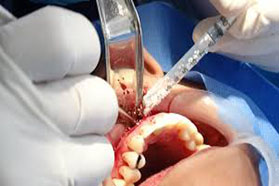

Para Extraer Piezas, Reponer Tejidos o Colocar Implantes

La cirugía oral generalmente se aplica para extraer dientes incluidos, raíces, quistes u otros procesos patológicos, aunque también es necesaria para reponer tejidos perdidos (hueso o encía) o para la colocación de implantes dentales que servirán para reponer dientes perdidos.

Se realiza habitualmente con anestesia local, sin que se necesiten otros cuidados especiales, aunque te indicaremos las precauciones que debes tener en cuenta. El objetivo es evitar complicaciones que a veces pueden ser molestas, pero que normalmente se controlan bien con los tratamientos antibióticos, analgésicos y anti-inflamatorios adecuados.